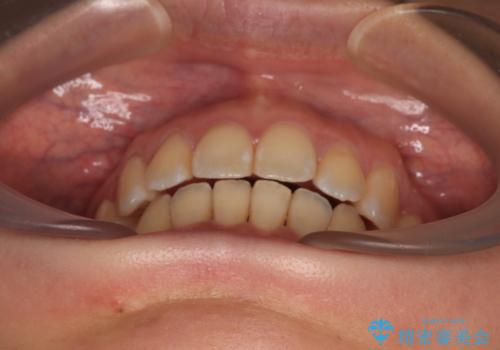

- 前歯の出っ歯と口元の閉じにくさを気にして来院された患者様です。

上下前歯の歯軸の角度が大きく改善され、お口を閉じたときに顎先に認められた梅干し様の皺も改善されました。